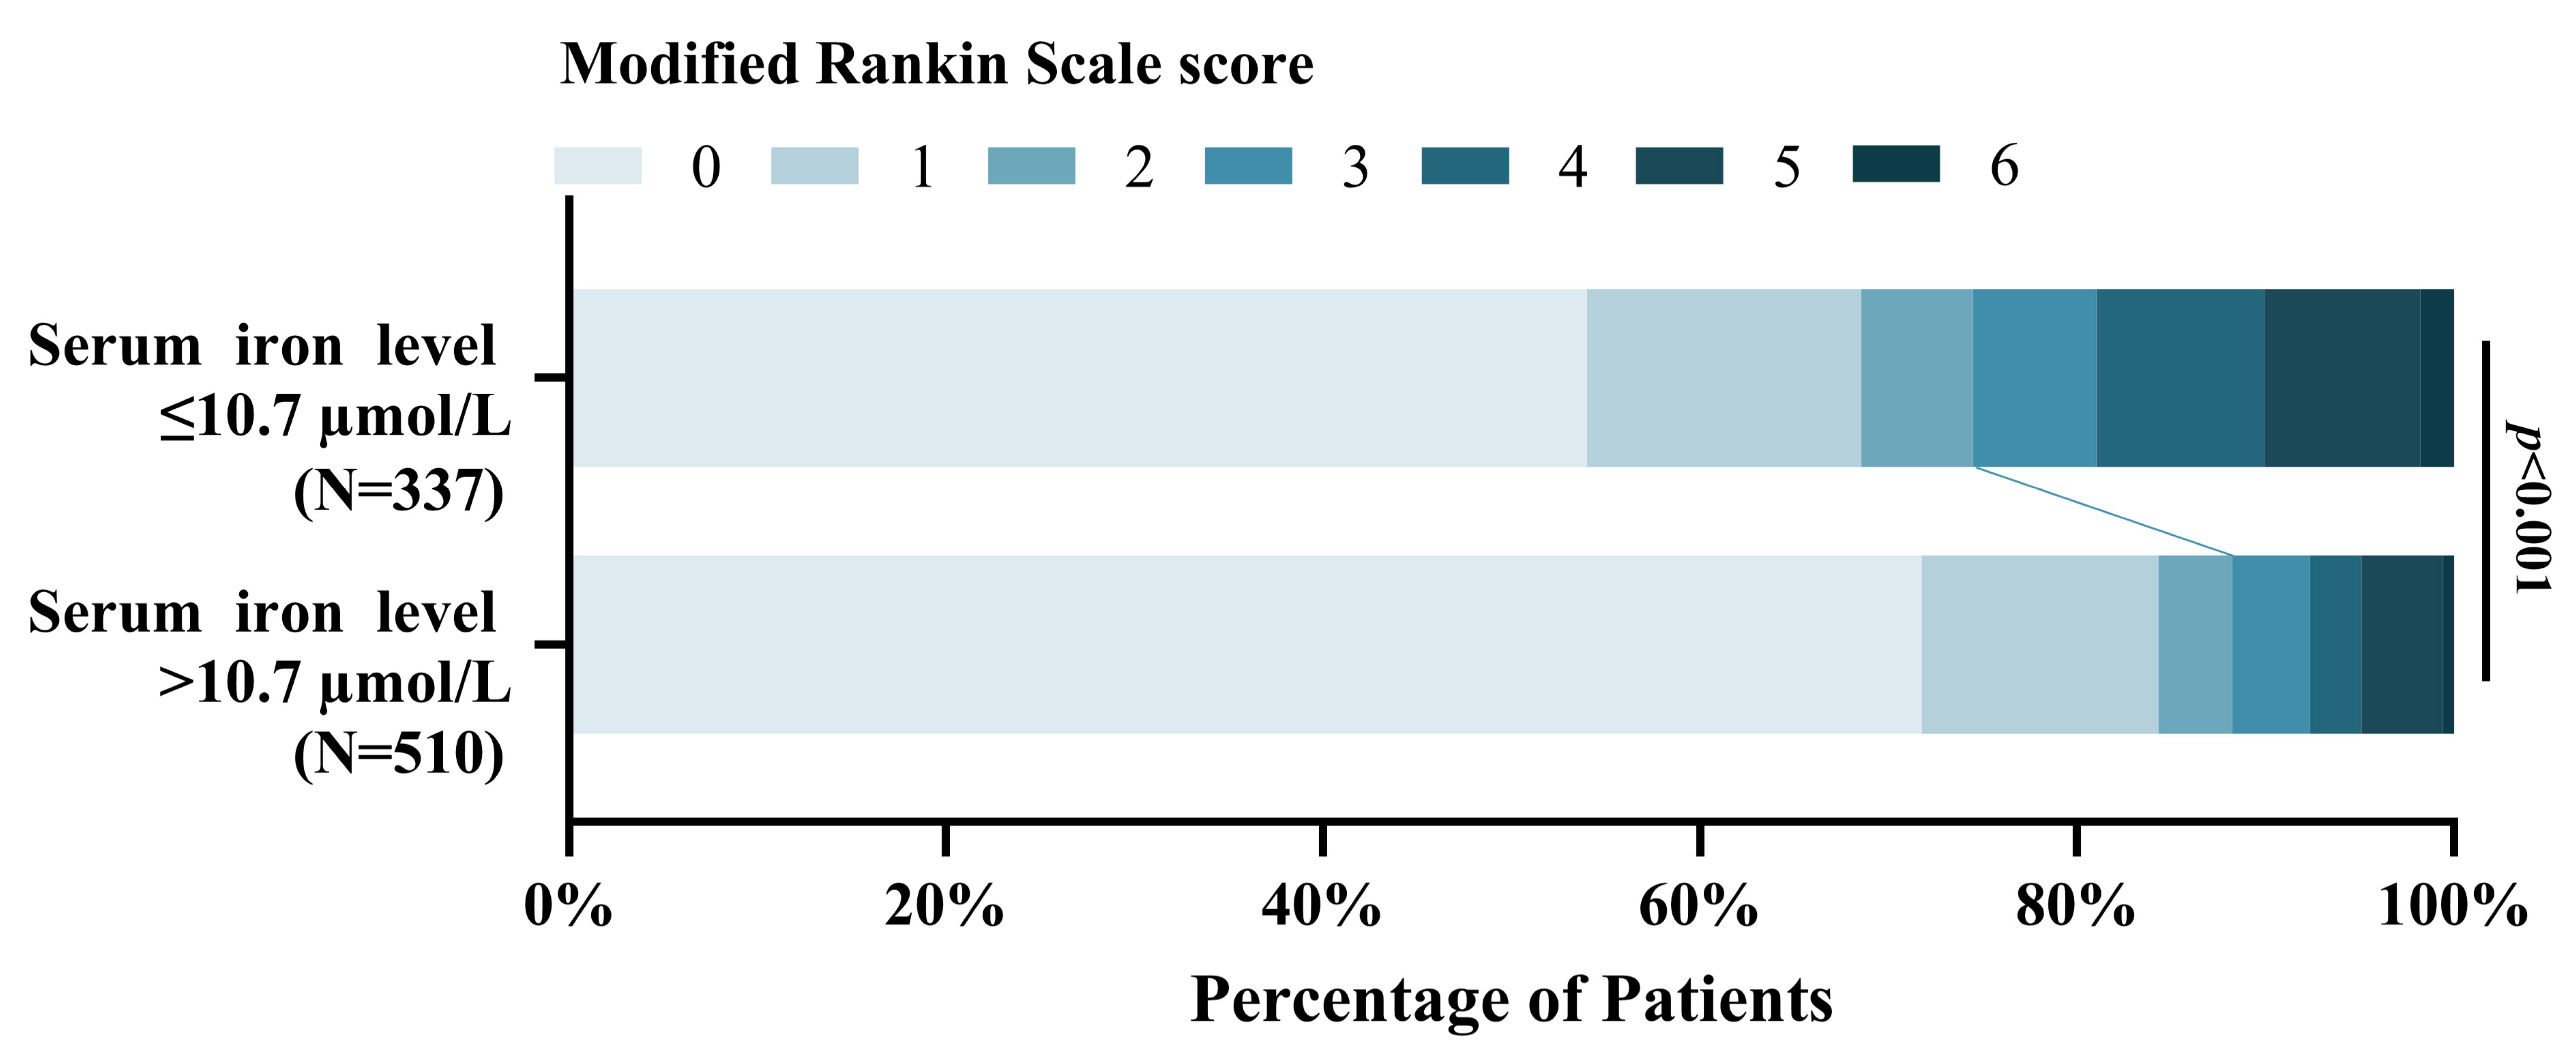

4.4. Association of Serum Iron with Poor 3-Month Functional Outcome